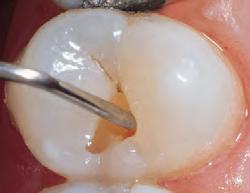

PROCEDURE

dentin) with slow-speed round bur or excavator. To control overexcavating near the pulp, remove final portion of caries with hand excavator.